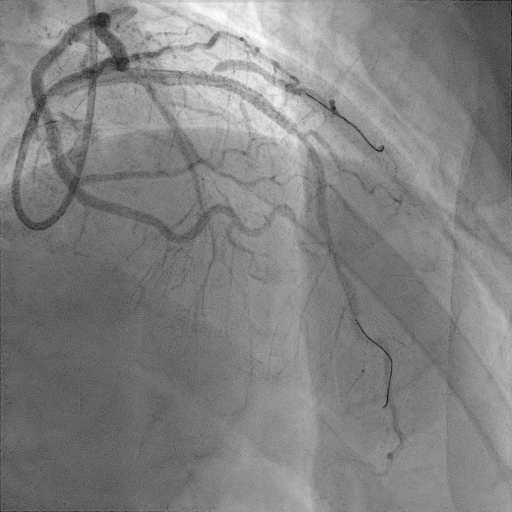

간단히 환자의 관상동맥 조영술 결과를 살펴보자

관상동맥조영술(coronary angiography) 결과 환자는 proximal LAD(left anterior descending)의 total occlusion으로 TIMI flow** 0점이었다.

관상동맥 협착으로 혈류량을 나타내는 지표인 TIMI flow로 0점은 혈관이 완전히 막혀서 혈류가 없는 상태, 3점은 정상 혈관으로 혈류가 완전한 상태를 타나 내며 0~3점 총 4단계로 표시한다.

병변의 위치에 중재술을 마친 환자는 시술 후 합병증 발생여부 및 치료를 위해 중환자실에 입원을 하였다.